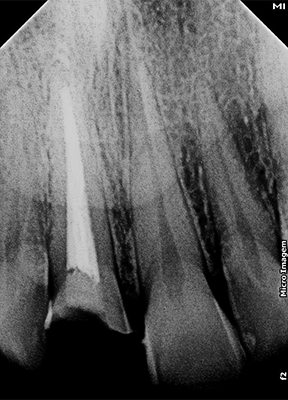

Após exame radiográfico inicial no dente 11, foi proposto a reabilitação com pino Whitepost System, cimentado com a combinação de sistema adesivo Ambar Universal APS e cimento Allcem Core, além de reabilitação coronária com resina composta Vittra APS. No dente 21 foi verificada a necessidade de reanatomizar, empregando faceta vestibular confeccionada com o sistema de resina composta Vittra APS.

3 | Radiografia Inicial do dente 11 demonstrando adequado tratamento endodôntico e selamento com cimento de ionômero de vidro